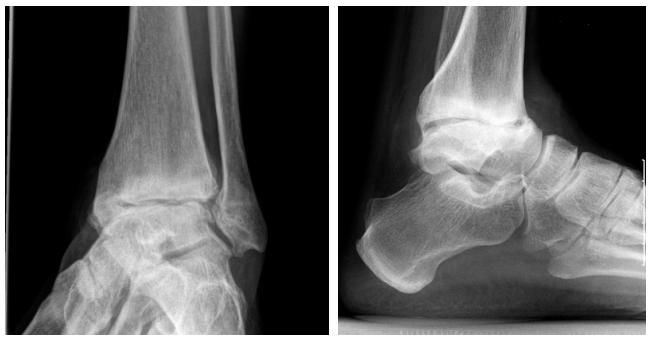

Прежде чем начать лечение воспалительного процесса, необходимо установить точный диагноз. Для этого проводятся следующие мероприятия:

- беседа с пациентом;

- осмотр пораженного сустава и окружающих тканей;

- физикальное обследование;

- компьютерная томография или магнитно-резонансная томография;

- рентгенографическое исследование;